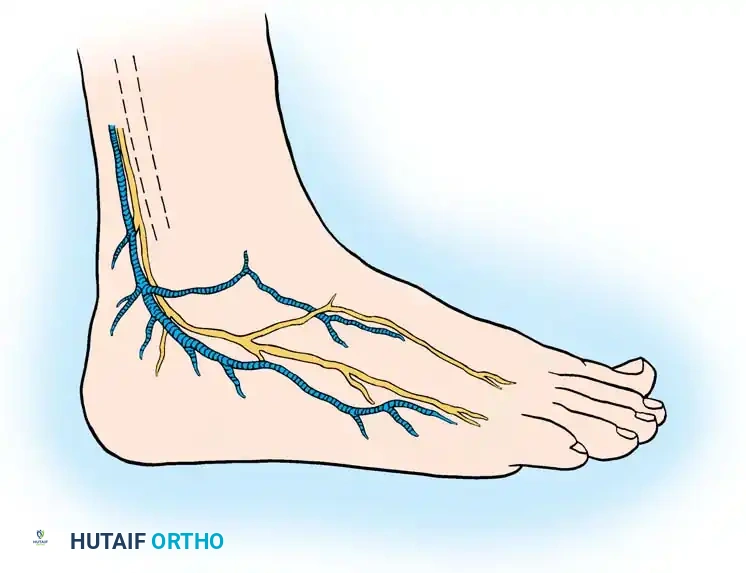

Begin the incision 10 to 12 cm proximal to the tip of the lateral malleolus, positioned approximately 1 cm posterior to the subcutaneous border of the fibula. Continue the incision distally and slightly obliquely to accommodate the bulbous posterior aspect of the lateral malleolus. Curve the incision gently 1 cm distal to the tip of the lateral malleolus, extending toward the base of the fifth metatarsal for another 3 to 4 cm.

Surgical Pitfall: The sural nerve and the small saphenous vein course just posterior to the peroneal tendons and are strictly subcutaneous at this level. Meticulous dissection is required to avoid iatrogenic neuroma formation, which can be more debilitating than the primary tendon pathology.